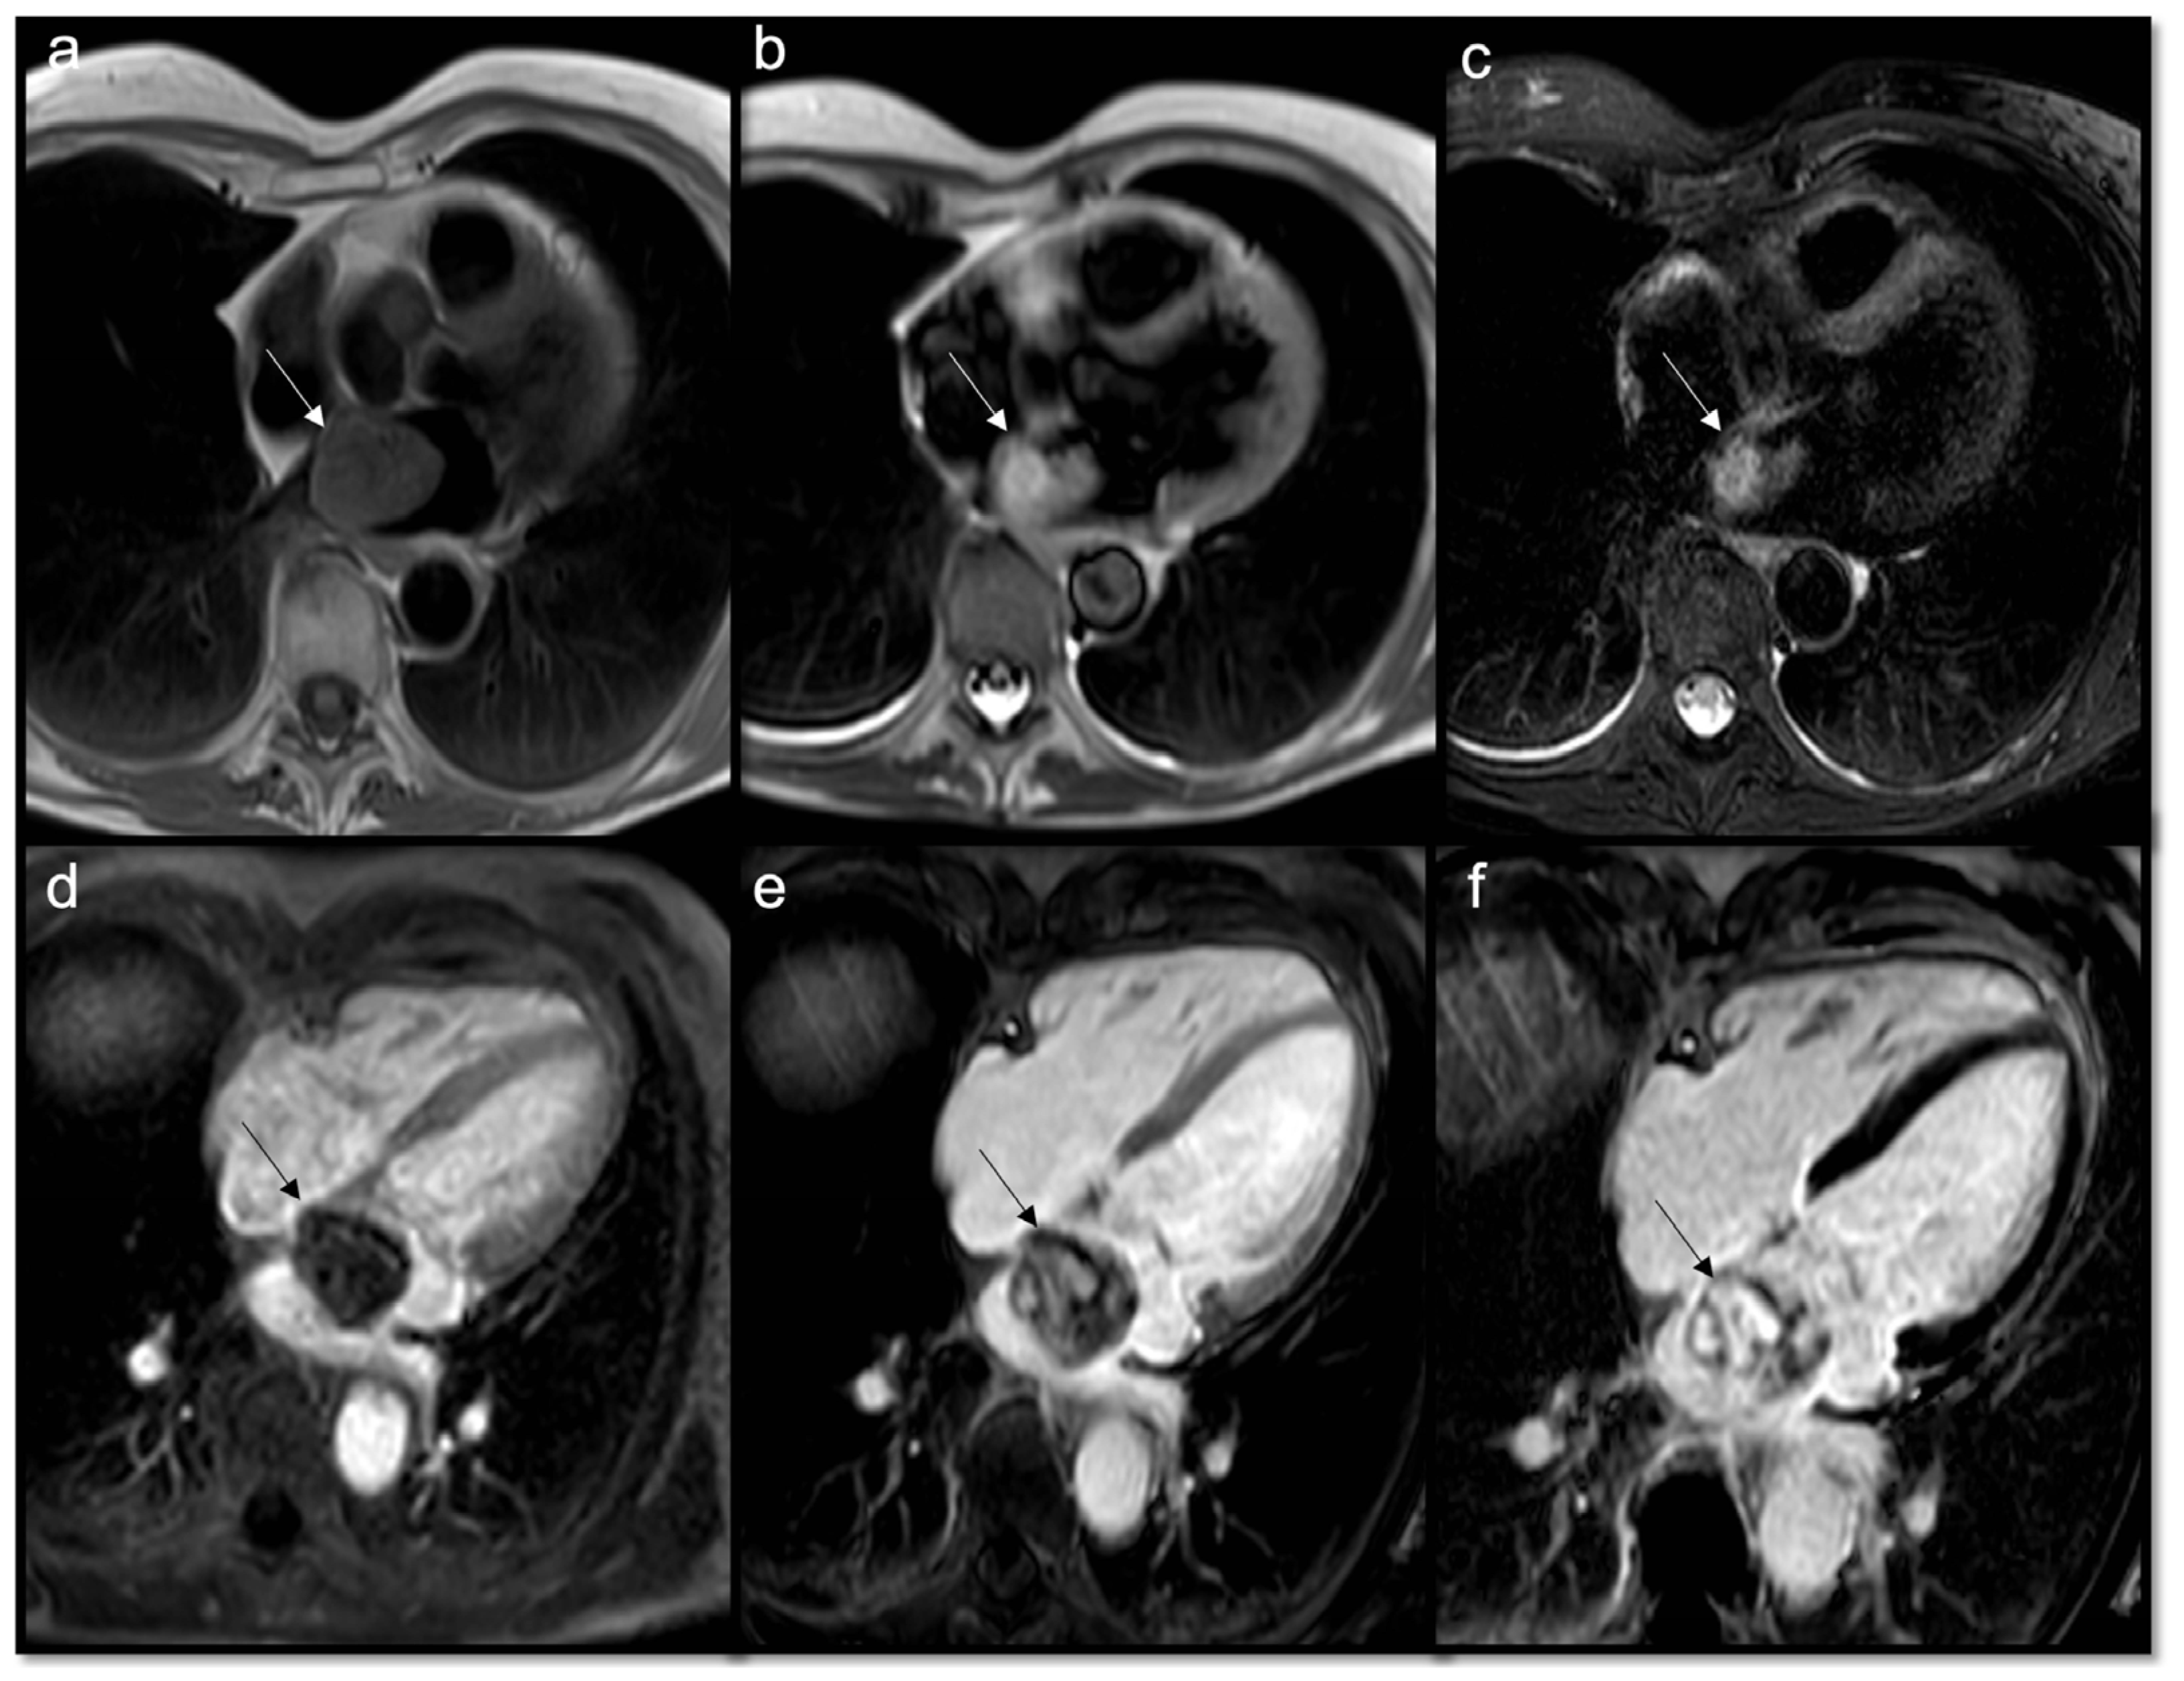

Figure 6.

Chagas Disease in a 67-year-old woman. The 2CH and 4CH (a,c) views demonstrate an LV apical aneurysm with intra-cavitary thrombi (arrows). Thrombi do not show enhancement on LGE images (b) and appear hypointense on T2 weighted sequence (d) with very low T1 native value (e). It shows no enhancement on first pass perfusion sequences due to their avascular nature (f).